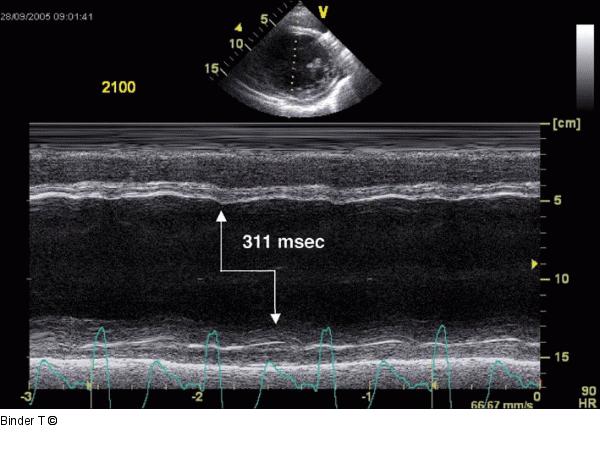

Abbildung 7: M-Mode linker Ventrikel - Septal-to-Posterior-Wall Motion Delay (SPWMD) M-Mode durch den linken Ventrikel: Die Einwärtsbewegung des Septums (Systole) und der posterioren Wand erfolgt zu unterschiedlichen Zeitpunkten (Dyssynchronie). Der enddiastolische Diameter ist mit 83 mm deutlich erhöht. Die Verkürzungsfraktion beträgt 12 %. Die systolische Linksventrikelfunktion ist deutlich reduziert. |

Abbildung 7: M-Mode linker Ventrikel - Septal-to-Posterior-Wall Motion Delay (SPWMD)